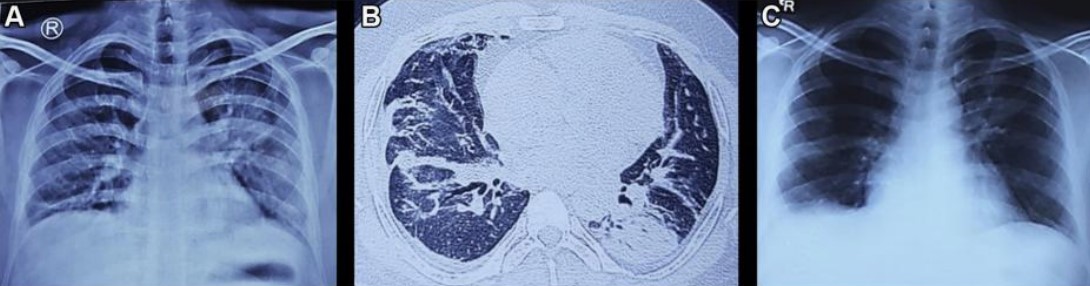

患者血液檢查結果見表1。患者白介素6(IL-6)升高,53pg/mL,鐵蛋白水平升高,515 ng/mL。胸片顯示左側中區和下區實變(圖2A)。心電圖顯示為竇性心動過速。床旁超聲心動圖檢查顯示左心室整體運動功能減退,射血分數降低40%~45%。胸部CT掃描顯示雙側不均勻的毛玻璃樣斑塊,以支氣管血管周圍為主,實變累及左下葉上段(圖2B)。腹部超聲與CT掃描及神經傳導檢查結果均正常。

圖2 A.患者入院時的胸片;B.入院后行胸部CT掃描;C.患者出院時的胸片

最初對患者進行補氧、理療和抗凝治療。在收到第一份血清降鈣素原報告前,醫生使用單劑量廣譜抗生素治療患者。并進行靜脈注射糖皮質激素(1 mg/kg潑尼松龍)和呋塞米(120 mg,分三次給藥)治療。同時監測患者液體出入量,平均動脈血壓維持在> 65 mm Hg。患者逐漸進行全天頻繁的被動和主動活動。住院的最初兩天患者發作了兩次低熱,第三天起患者退熱,并且其虛弱和低氧血癥開始改善,至第7天逐漸改善至就診前狀態。患者下肢肌力也恢復,氧飽和度恢復至99%,影像學異常也消失(圖2 C)。患者出院時活動自如,醫生建議其口服糖皮質激素2周。